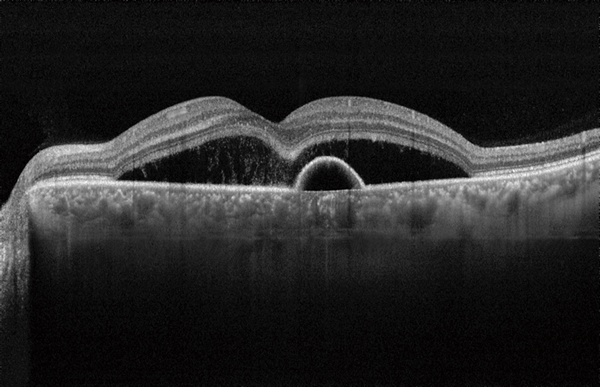

Оптическая когерентная томография (OCT) показывает различные виды патофизиологических изменений при ЦСХ, от появления субретинальной жидкости и отслойки пигментного эпителия до дистрофических изменений сетчатки при хронической форме течения заболевания. OCT особенно полезна в идентификации незначительных и даже субклинических отслоек сетчатки в макулярной зоне.